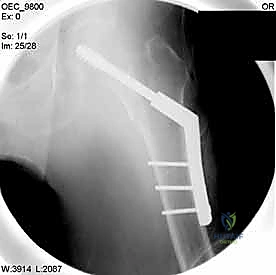

الخيارات الجراحية الحديثة لعلاج كسور الورك المدورية

يعتمد اختيار نوع الجراحة على شكل الكسر، مدى تفتته، وجودة عظام المريض. يتقن الدكتور محمد هطيف أحدث تقنيات التثبيت الداخلي العالمية.

| وجه المقارنة | الشريحة والمسمار المنزلق (DHS - Dynamic Hip Screw) | المسمار النخاعي القريب (PFN - Proximal Femoral Nail) |

|---|---|---|

| آلية العمل | شريحة معدنية تُثبت على السطح الخارجي للعظم مع مسمار كبير يخترق عنق الفخذ. | مسمار من التيتانيوم يُدخل داخل التجويف النخاعي للعظم (من الأعلى) مع مسامير عرضية للتثبيت. |

| نوع الكسور المناسبة | الكسور المستقرة (Stable Fractures) ذات التفتت البسيط. | الكسور غير المستقرة (Unstable)، المفتتة بشدة، أو التي تمتد لأسفل العظم. |

| الشق الجراحي | شق جراحي جانبي أطول نسبياً (حوالي 10-15 سم). | جراحة طفيفة التوغل، شقوق صغيرة جداً (Minimally Invasive). |

| الميكانيكا الحيوية | يوفر ضغطاً ديناميكياً ممتازاً على موقع الكسر أثناء المشي. | يوفر دعماً ميكانيكياً أقوى لأنه يقع في مركز ثقل العظم (محور تحمل الوزن). |

| فقدان الدم | أكثر نسبياً مقارنة بالمسمار النخاعي. | أقل بكثير. |

| سرعة التعافي | ممتازة، ولكن قد تتطلب حذراً أكبر في الكسور غير المستقرة. | أسرع، ويسمح بتحميل الوزن في وقت أبكر في الحالات المعقدة. |

بناءً على التقنية المختارة (DHS أو PFN)، يقوم الجراح بعمل شق دقيق. في تقنية المسمار النخاعي، تكون الشقوق صغيرة جداً للحفاظ على الأنسجة الرخوة وتقليل النزيف.

4. إدخال السلك الدليلي (Guide Wire)

يتم إدخال سلك معدني رفيع جداً عبر العظم باتجاه رأس الفخذ تحت توجيه الأشعة المستمر. هذا السلك يعمل كمسار دقيق سيتبعه المسمار النهائي. يجب أن يكون السلك في الموضع الهندسي المثالي لتجنب اختراق مفصل الورك.

5. الحفر وتثبيت الغرسة (Reaming and Implantation)

يتم استخدام أداة حفر مجوفة تمر فوق السلك الدليلي لتوسيع مسار في العظم. بعد ذلك، يتم إدخال المسمار الرئيسي القوي (سواء المسمار المنزلق أو المسمار النخاعي).

6. التثبيت النهائي (Locking)

لضمان عدم تحرك الغرسة، يتم تثبيتها بمسامير إضافية أصغر في جسم عظم الفخذ. هذه المنظومة الميكانيكية توفر ثباتاً استثنائياً يسمح للمريض بتحريك ساقه فور استيقاظه من التخدير.

مجموعة من الصور الإضافية التي توضح مراحل دقيقة من العمل الجراحي المعقد الذي يجريه الأستاذ الدكتور محمد هطيف لضمان أعلى درجات الدقة الميكانيكية الحيوية: